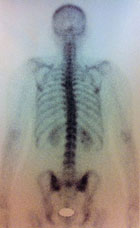

Mme T., née en 1979, présente des dorsalgies d’horaire mixte depuis plusieurs années.

La radiographie est normale. Devant la persistance des douleurs, une scintigraphie osseuse est prescrite.

Le radiologue signale une hyperfixation gauche de T5.

Une IRM est alors prescrite :